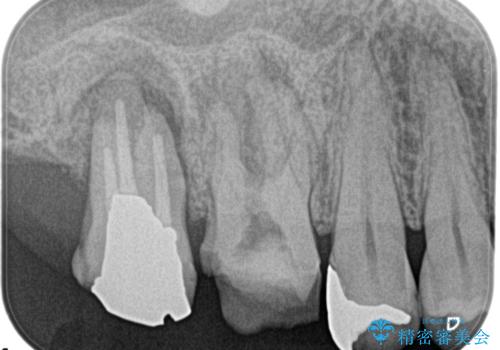

奥歯が痛い。精密根管治療〜オールセラミッククラウン

奥歯の根管治療~オールセラミッククラウン

根管治療の注意事項(リスク・副作用など)

- 根管治療により類似の全ての症例の問題が解決するわけではなく、症例はあくまでも一例です

- 根管治療により痛みや腫れがひかない事や、術後に痛みや腫れが生じる事、治療によるファイル破折やパーフォレーションなどの偶発症、術後の歯根破折を生じる可能性もあります